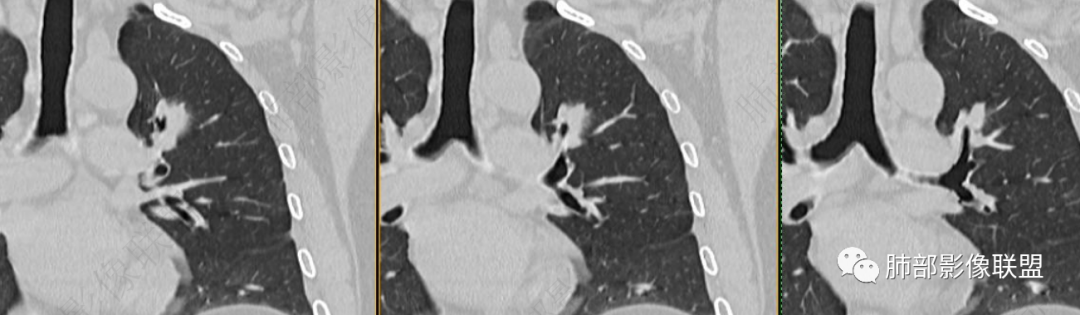

2、病灶以实性密度为主,前、外侧蔓延,GGO部分边界清楚,部分欠清

支气管未见受明显侵犯,未见阻塞,壁增厚,狭窄或扩张。

软组织+重建;病灶实性部分不是类圆形,密度相对均匀柔和。